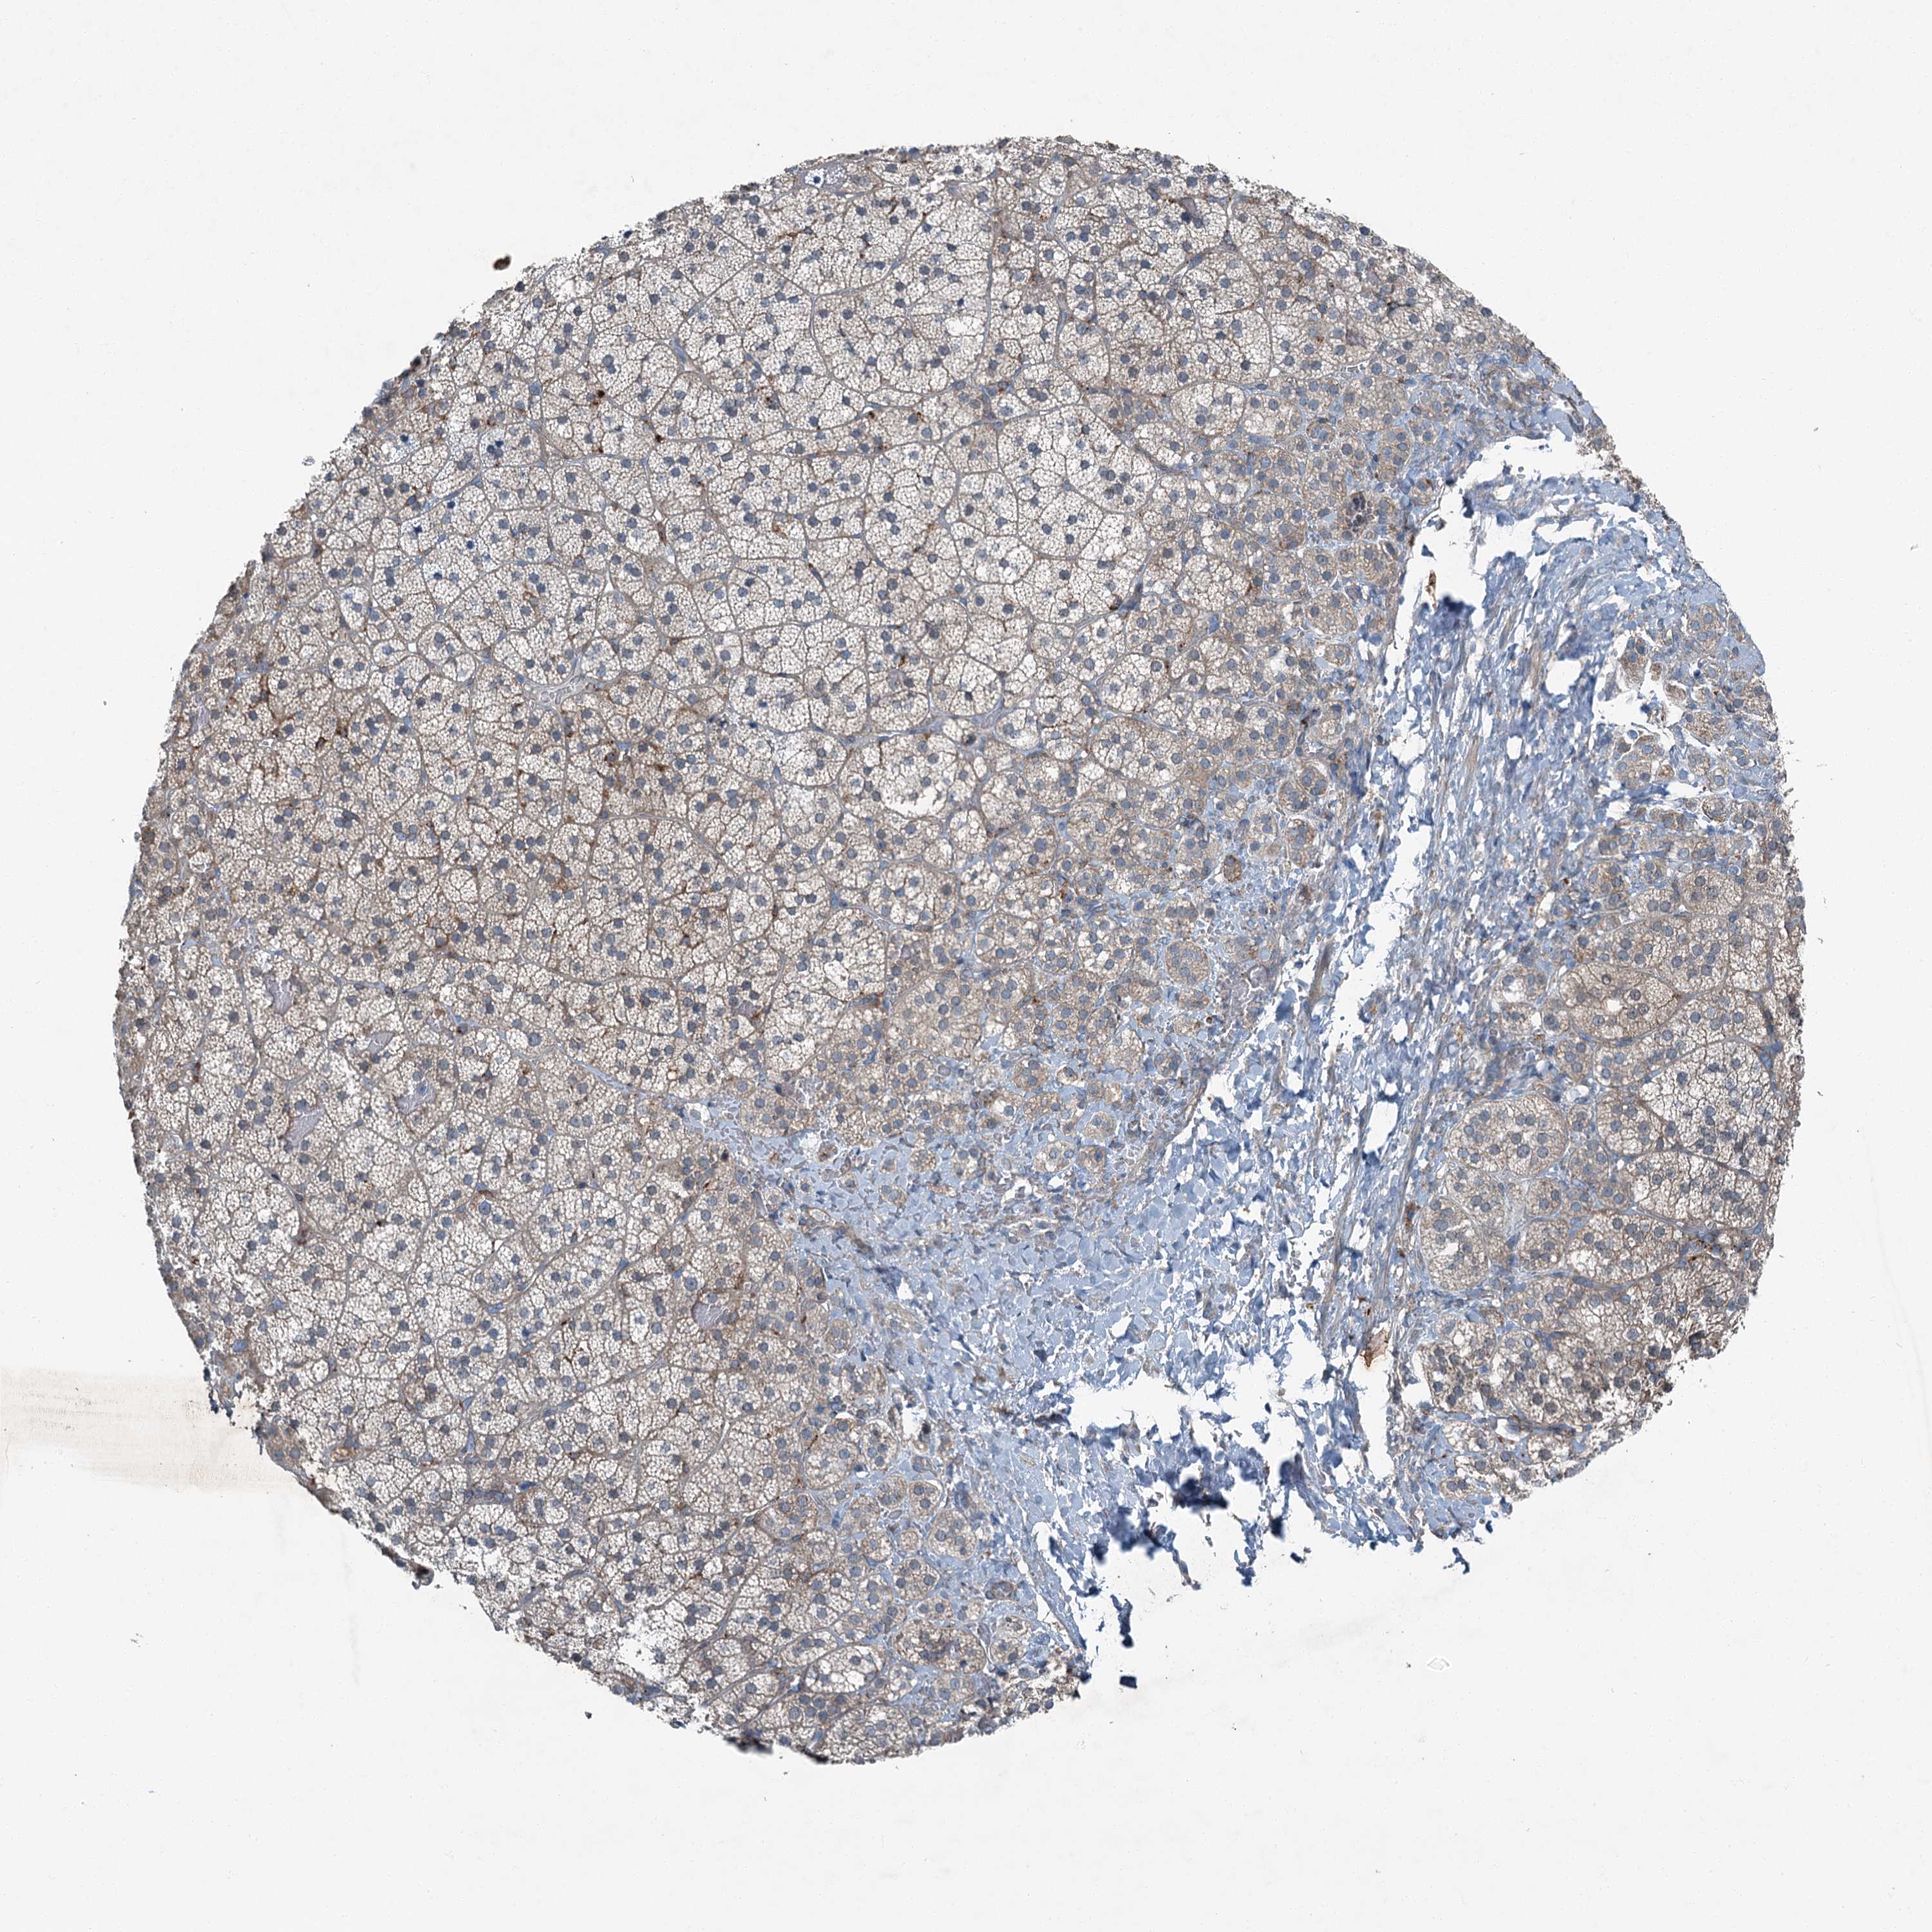

ADRENAL GLAND - Antibody stainingi

Antibody staining in the annotated cell types in the current human tissue is reported as not detected, low, medium, or high, based on conventional immunohistochemistry profiling in selected tissues. This score is based on the combination of the staining intensity and fraction of stained cells.

Each image is clickable and will lead to virtual microscopy that enables deeper exploration of all samples and also displays staining intensity scores, fraction scores and subcellular localization as well as patient and tissue information for each sample.

Antibody HPA037422Antibody HPA037423Antibody CAB032501

Glandular cells Not detectedNot detectedMedium